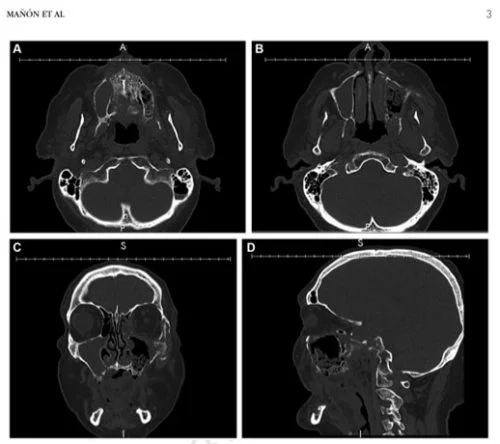

Es una complicación muy rara pero está asociada a la hipercoagulabilidad o estado protrombótico o trombofilia que conlleva a trombosis de vasos sanguíneos debido a una anomalía en el sistema de coagulación. Existen pocos casos reportados sobre necrosis y de osteomielitis maxilar mandibular asociada a Covid-19 pero bien sabemos que el virus y sus complicaciones es un tema que sigue en estudio constante. En este caso en particular la necrosis ocurrió por oclusión de la arteria maxilar izquierda.